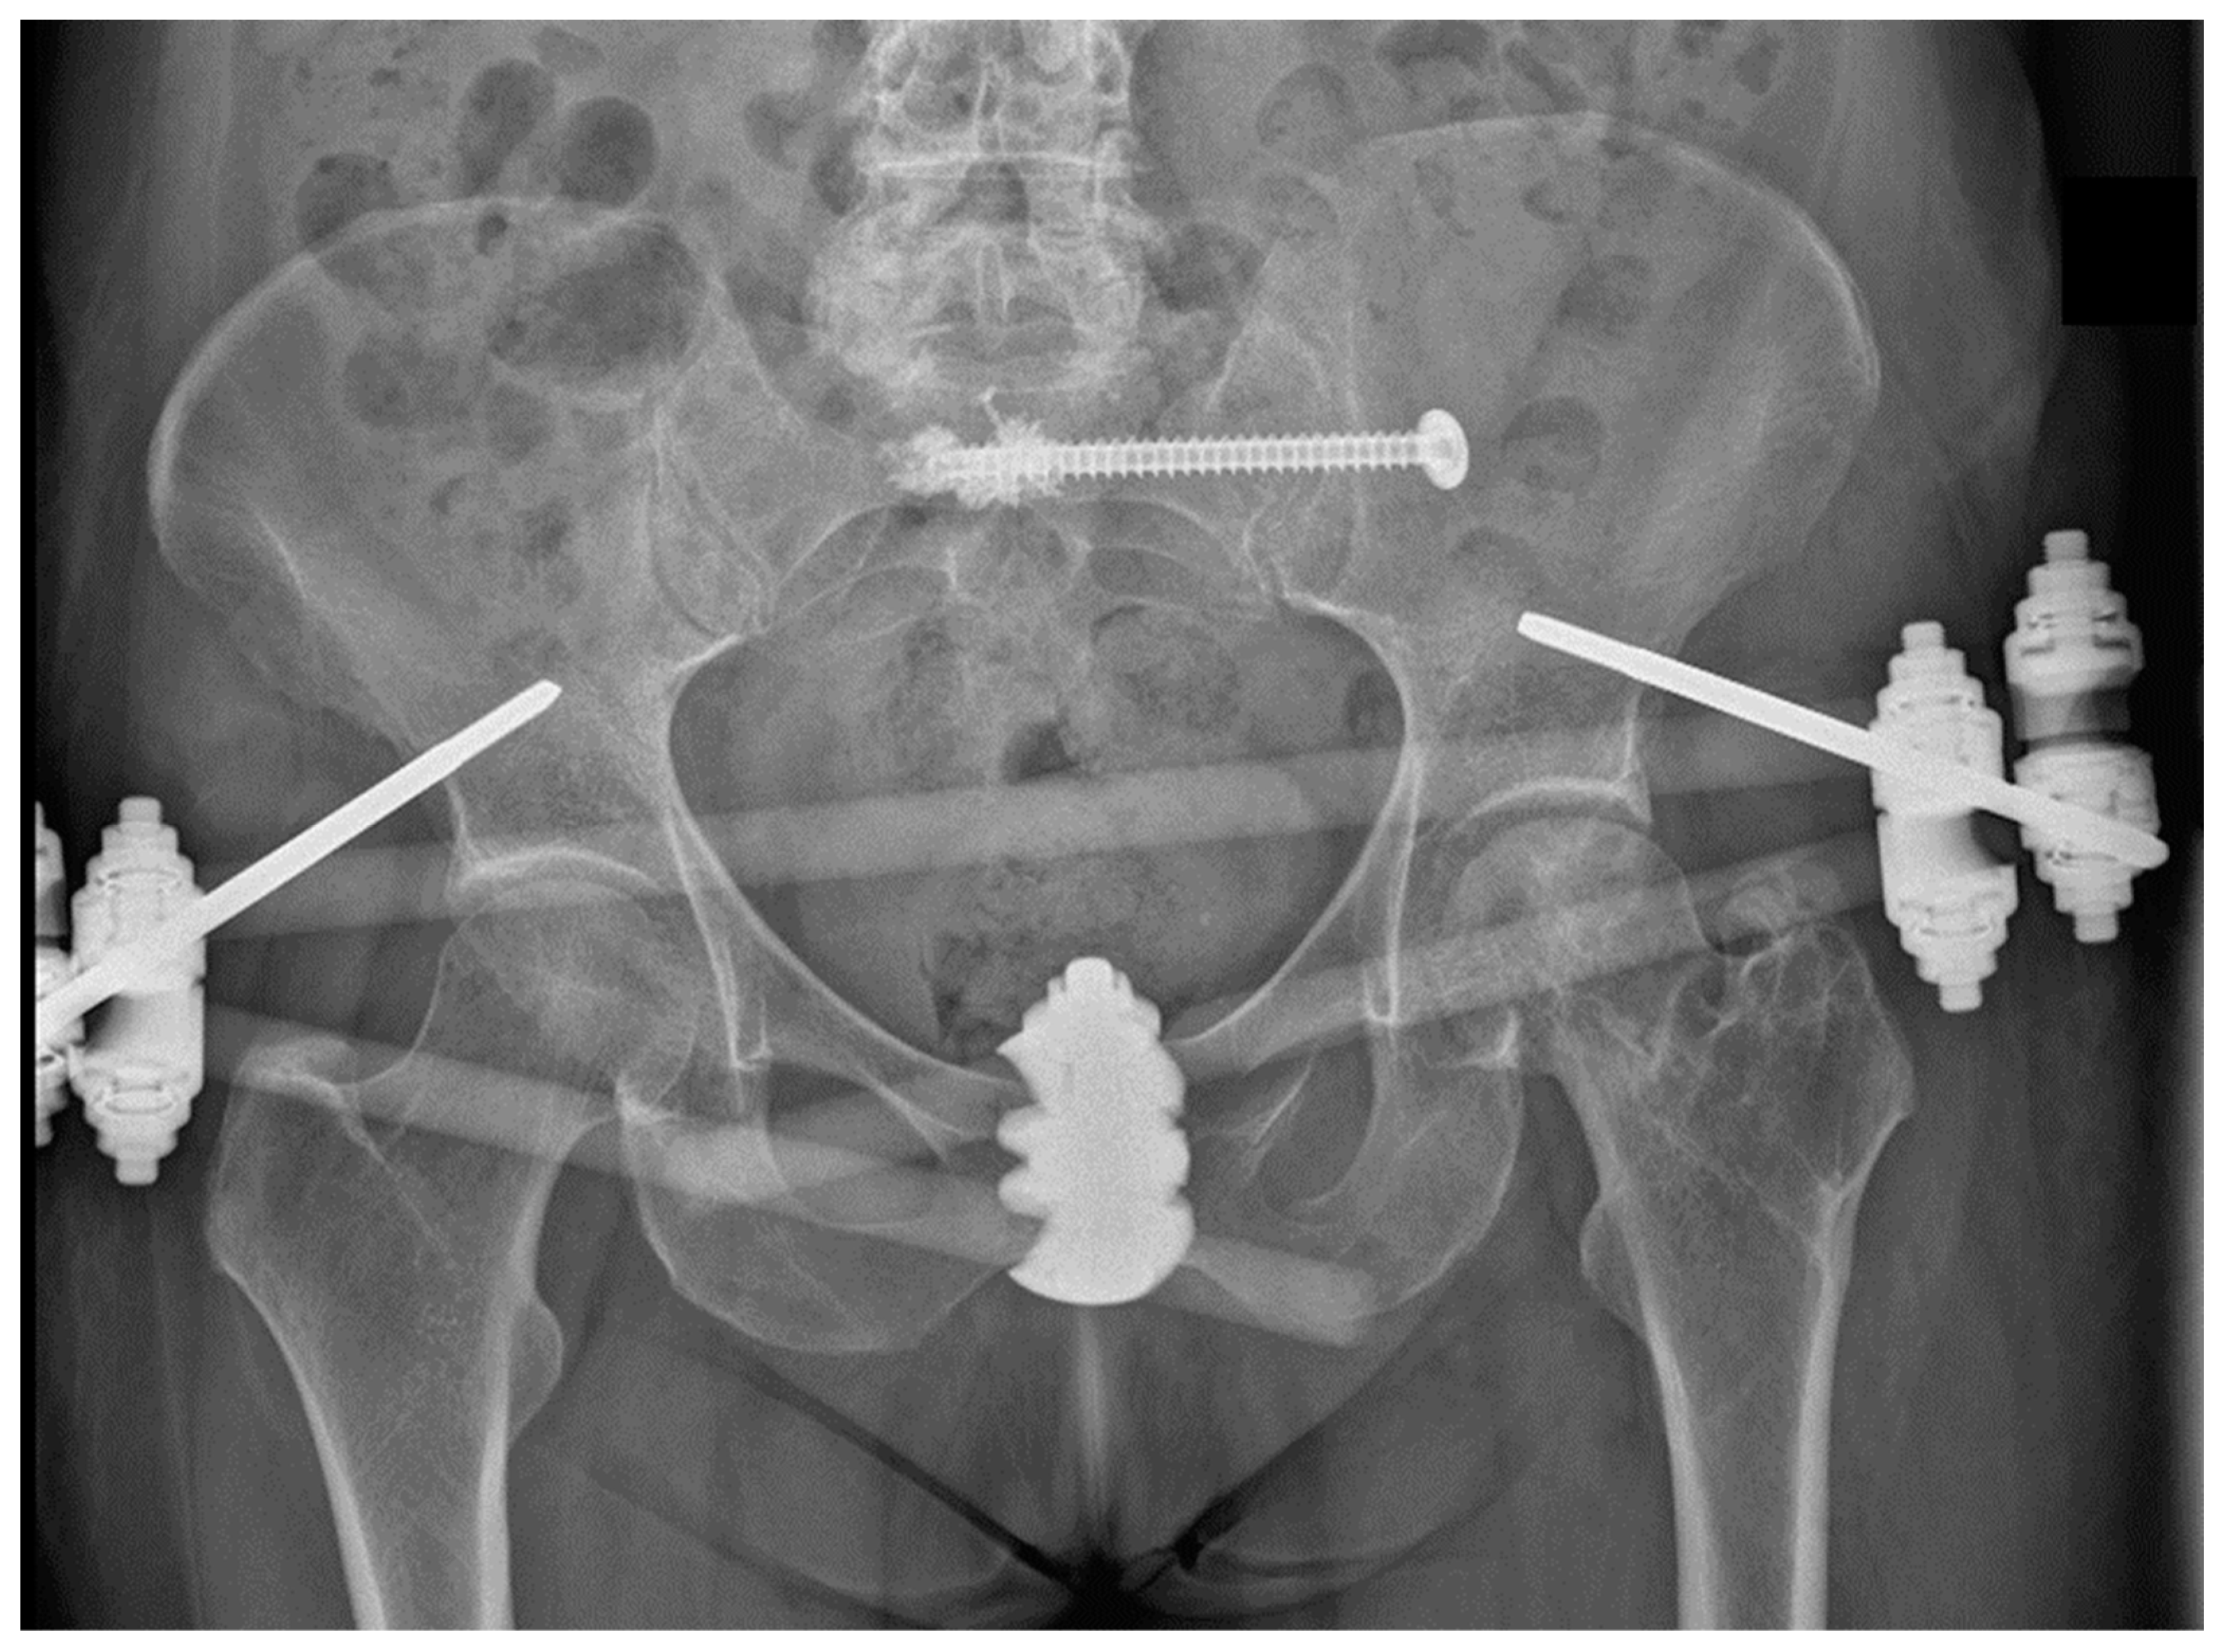

2. Materials and Methods

2.1. Biomechanical Testing